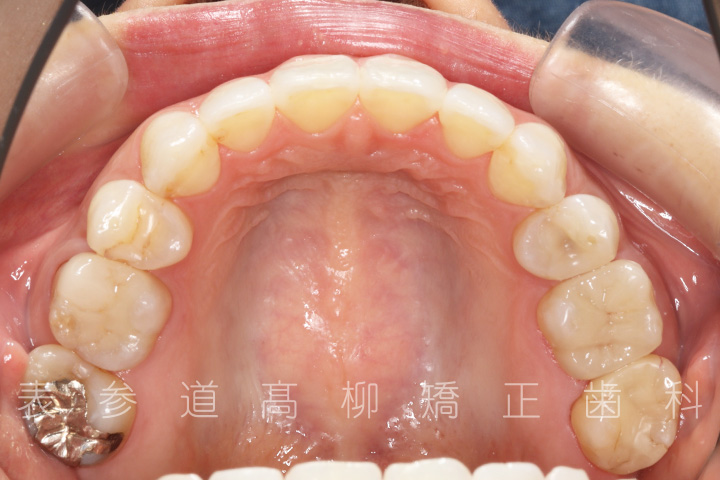

口呼吸と舌癖で前歯が咬み合わない患者様の症例をご紹介いたします。

• 治療終了

術前術後の比較